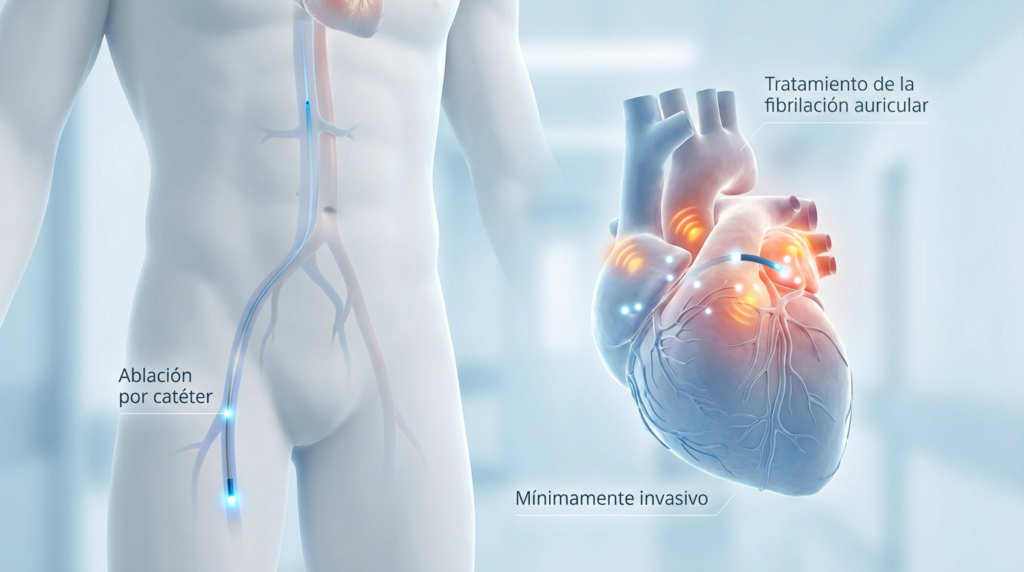

¿Qué es la ablación por fibrilación auricular?

La ablación por FA es un procedimiento mínimamente invasivo que busca aislar o eliminar los focos eléctricos anormales que desencadenan y mantienen la arritmia.

🔹 Se realiza mediante catéteres introducidos por la ingle

🔹 Permite corregir el problema desde su origen eléctrico

🔹 No es cirugía abierta

🔹 No deja cicatrices visibles

🔹 No produce dolor durante el procedimiento

🔹 Éxito de curar la arritmia arriba de un 85%

El objetivo no es “controlar” la fibrilación, sino restablecer el ritmo normal del corazón cuando el perfil del paciente lo permite.